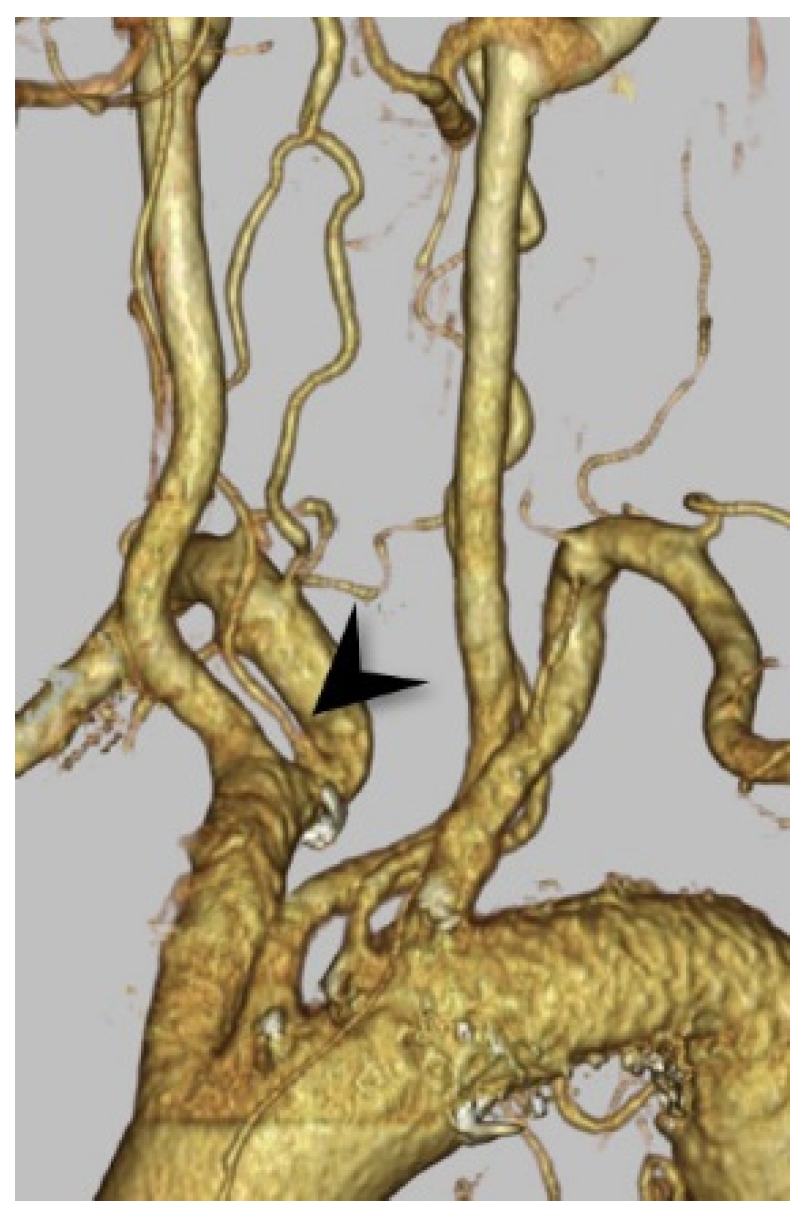

3.1. Right VA Originating from the Aortic Arch (Aortic Origin)

3.2. Right VA Originating from the Common Carotid Artery or the Brachiocephalic Artery

3.3. The Dual Origin of the Right Vertebral Artery